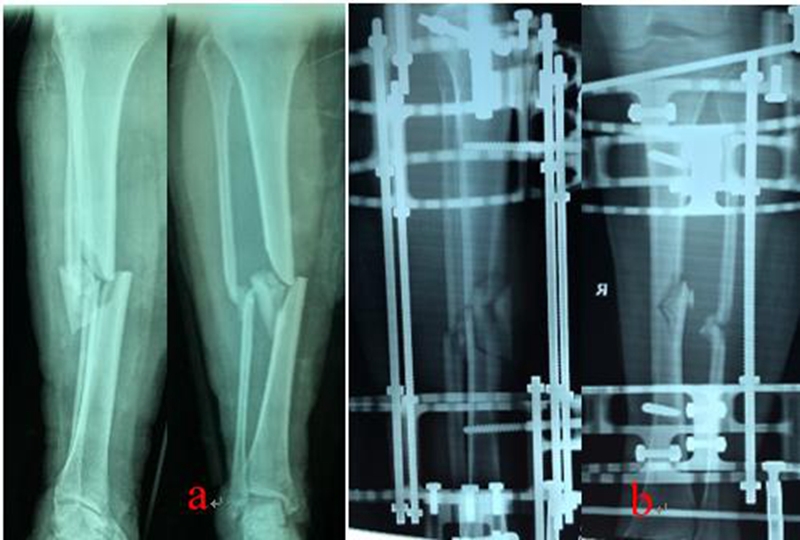

Liu等[4]采用临时性六轴支架治疗23例胫骨干骨折单边支架术后力线不佳的病例,所有病例均在2周内更换六轴支架,力线矫正满意后再更换为单边支架作为终末治疗,结果显示平均矫正时间为4天,最终均获得良好的骨折对位。Patel等[5]回顾性分析75例胫骨严重开放性骨折的病例资料,其中26例为Gustilo-Anderson 3A,47例为3B,2例为3C;9例采用髓内钉内固定,61例采用泰勒空间支架固定,5例采用Masquelet技术(髓内钉、二期植骨),结果显示感染率为6.7%,不愈合率4%,再骨折率2.7%,整体保肢率98.7%,作者认为1-3A型开放性骨折可以使用髓内钉内固定治疗,3B/C最佳治疗是环形外固定。Liu等[6]采用六轴支架治疗25例高能量胫骨干骨折,通过3D重建和Mimics软件模拟骨折复位和畸形矫正,通过电子处方复位骨折,均获得良好的骨折对位和功能恢复,作者认为此治疗方法适用于严重软组织损伤无法内固定治疗的复杂病例。

乔锋等[7-9]利用自主研发的3D打印骨科外固定架(QF)和数字六轴外架(QSF)治疗胫骨骨折,获得良好的临床疗效。3D打印骨科外固定架具有自动复位骨折功能,4根螺纹连接杆与骨的轴线平行,通过旋拧调节螺母,调节两个固定环之间的距离,实现对骨折断端轴向应力的调节和固定方式的转换,早期坚强固定,中期加压固定,后期弹性固定。复位过程无需透视,不依赖医生经验,手术时间短,可以不用麻醉,术后即可完全负重下地行走,复位精确,固定合理,操作简便。数字六轴外架QSF配套软件基于CT数据,与国际同类产品比较,复位精确,固定牢靠,操作简便,学习曲线短。

图1:QF治疗胫腓骨骨折

图2:QSF治疗胫腓骨骨折